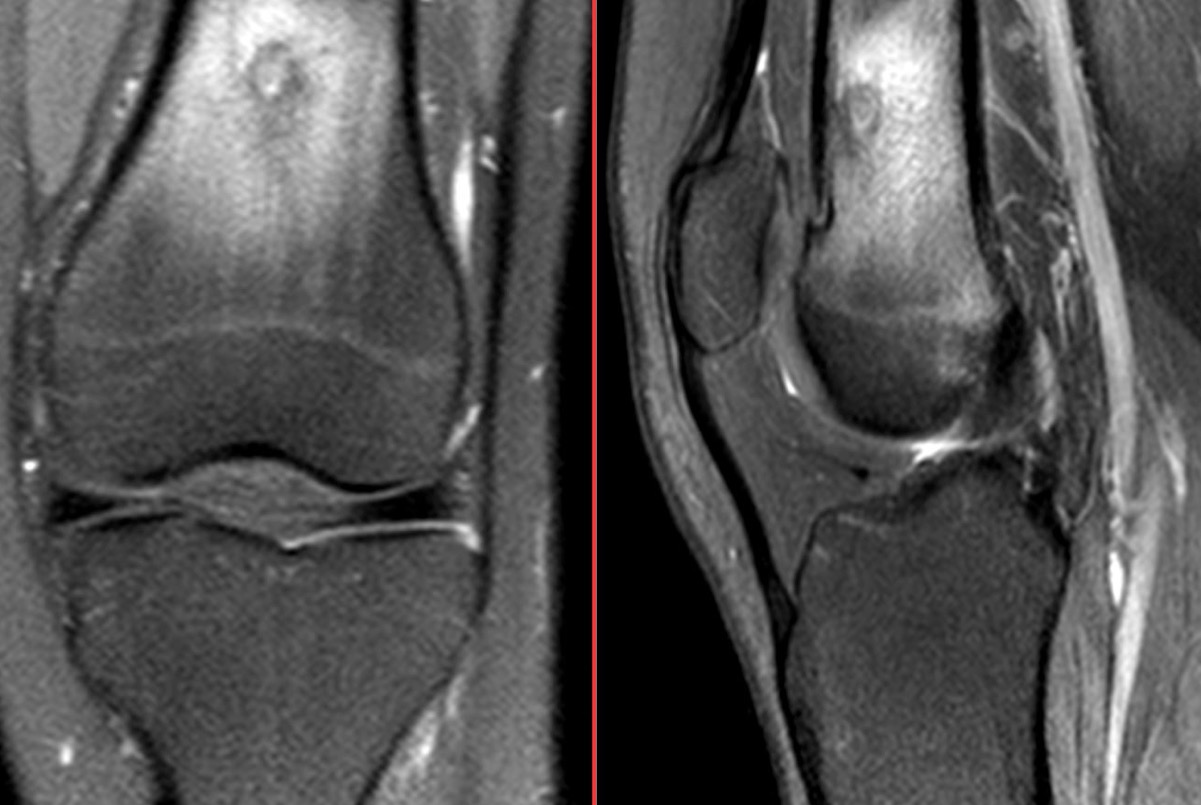

Figure 5 for case osteoid osteoma ( RID4005 )

Figure 5

Osteoid osteoma in cancellous (medullary) bone lacks the usual osteoblastic reaction that accompanies the classical cortical or juxtacortical osteoid osteoma.